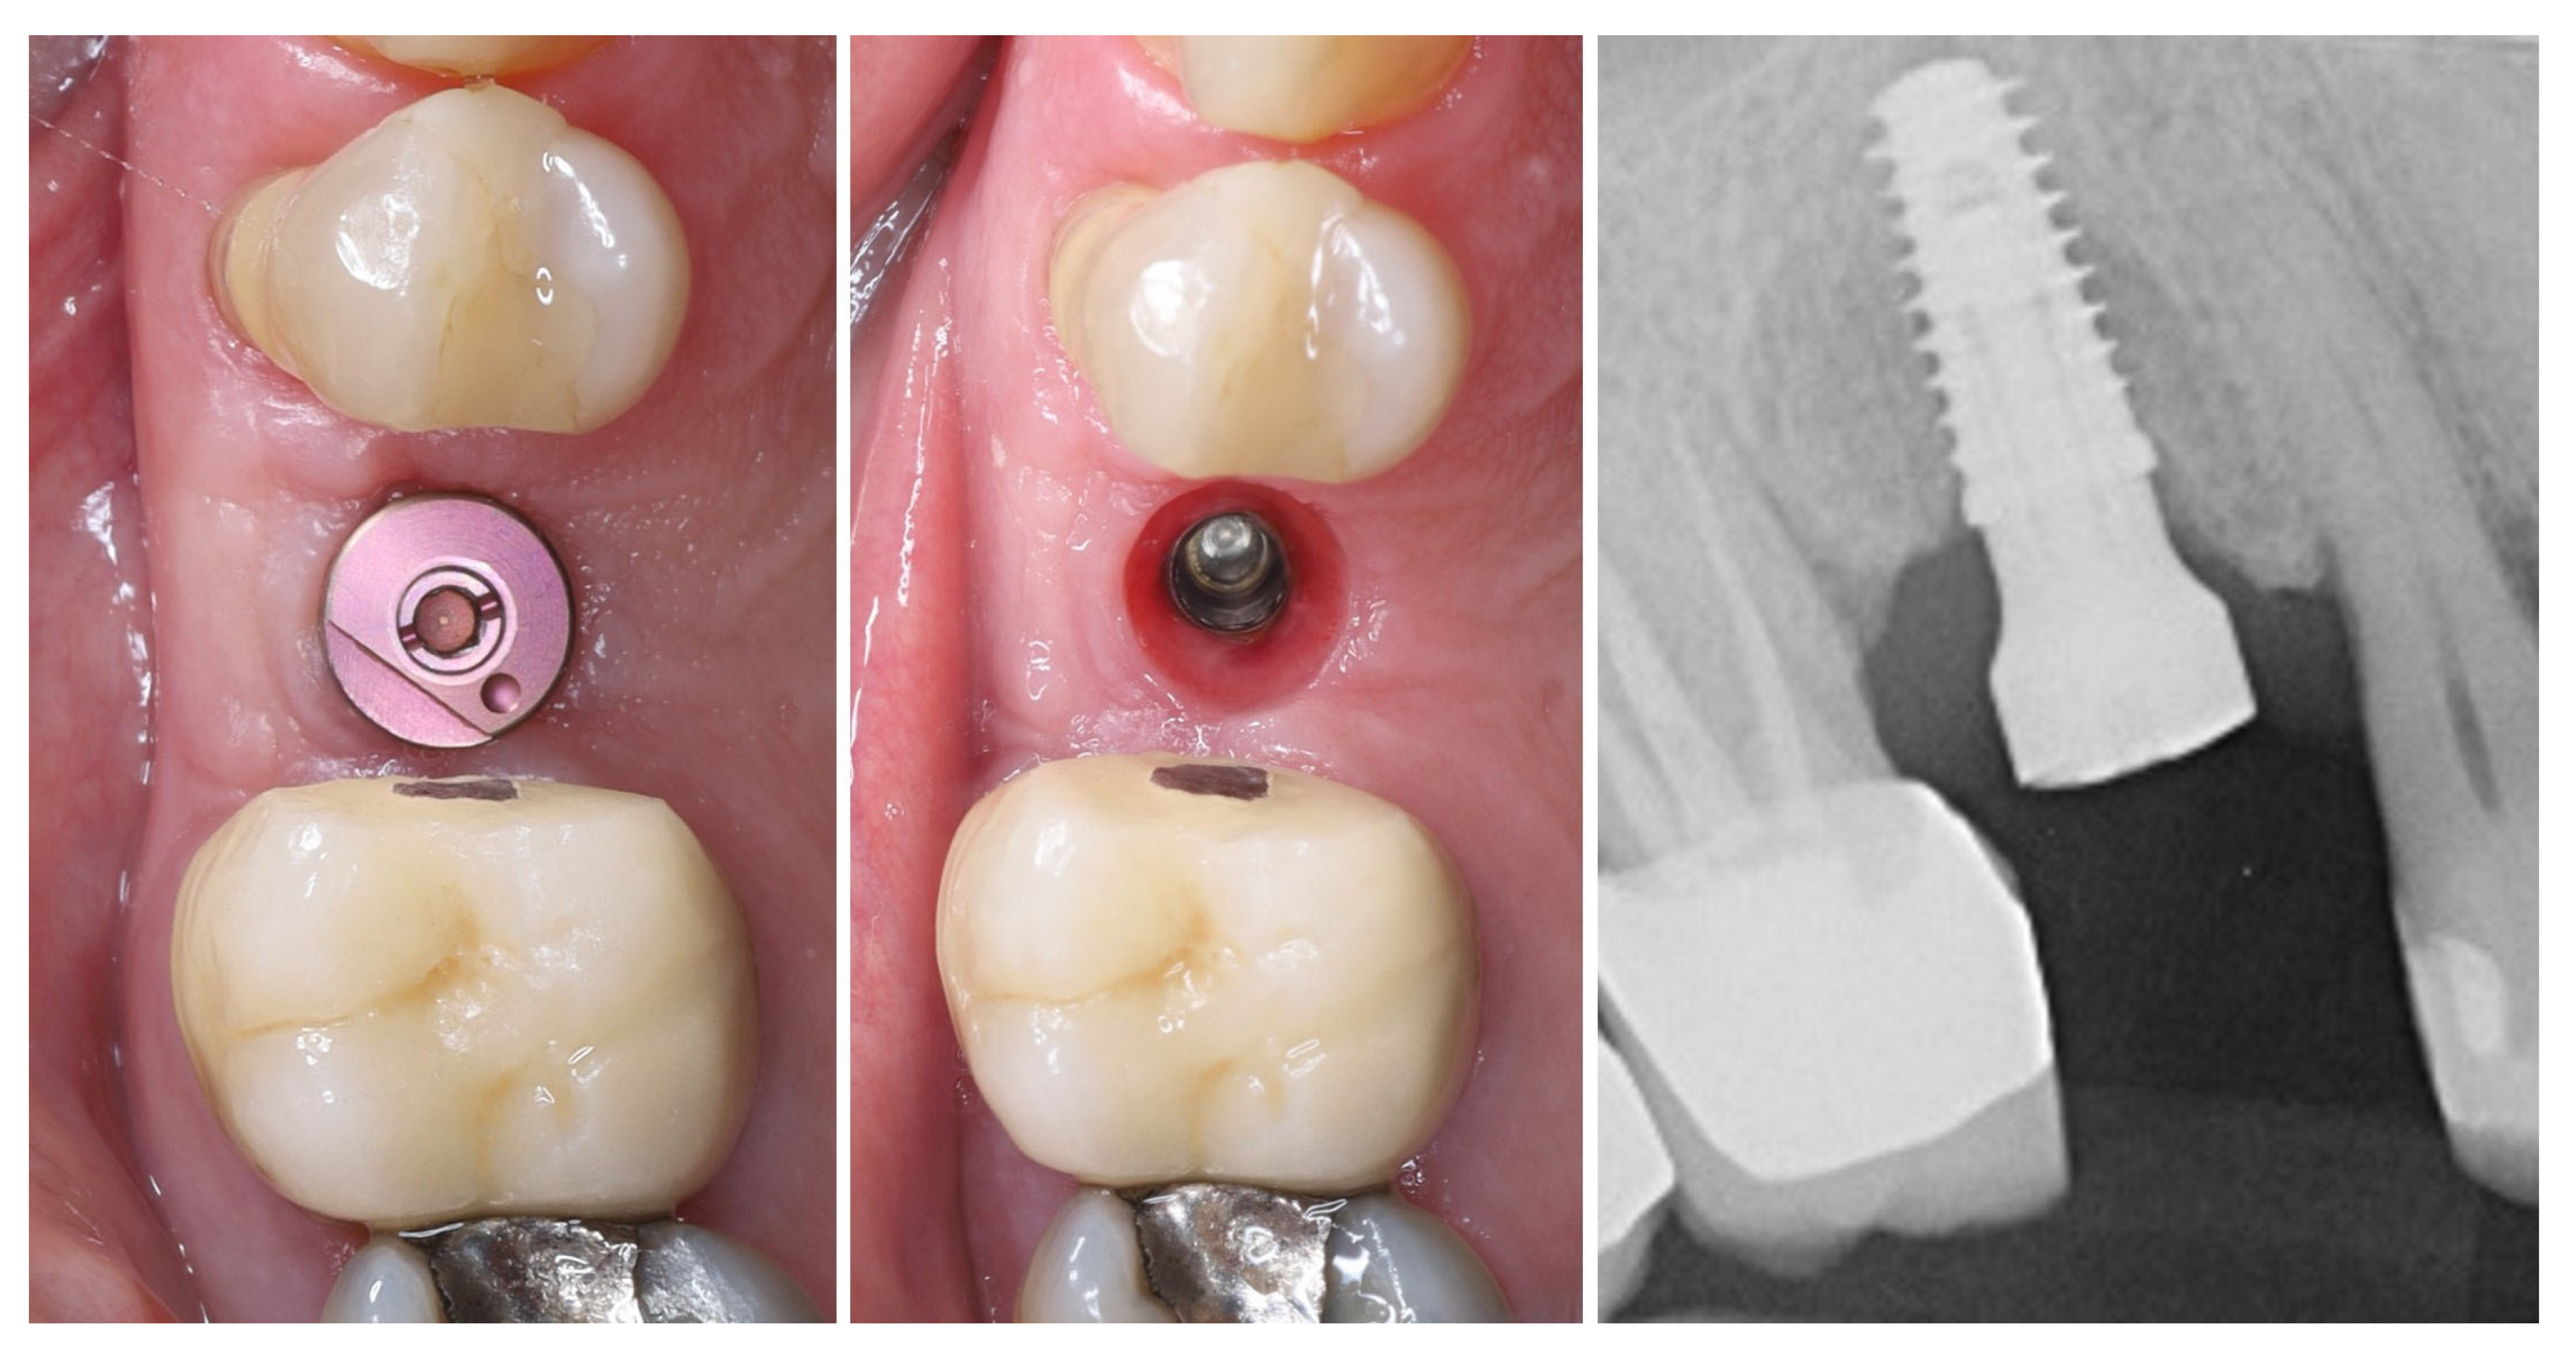

2. Materials and Methods—Clinical Case

| 1 | Baseline (Day 0) | 2.3 | 2.4 | Initial thin buccal tissue |

| 2 | 2 weeks post-op | Uneventful healing, stable mucosal margin | ||

| 3 | 3 months post-op (with provisional) | 3.4 | 3.4 | Increased thickness, stable bone and mucosa |